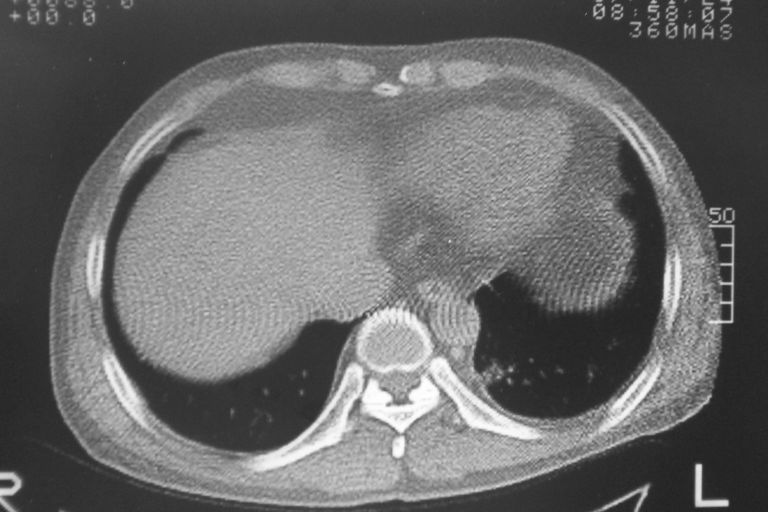

患者 男 50岁 无痛性咯血3天,无其他不适.

2心包积液

2、心包积液

2 心包积液。

左下肺结节状软组织密度影,一个边缘有卫星病灶,邻近胸膜增厚.另一个有毛刺.心影周围水样密度影环绕.考虑:

1.肺癌可能.肺tb待排.

2.左侧胸膜增厚.心包积液.

2心包积液,